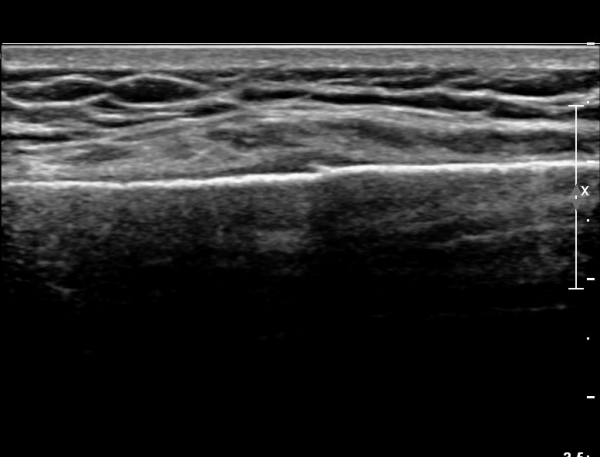

ŽÃËÀÚ¸¦ ¾à°£ ¸»´ÜÀ¸·Î À̵¿ÇÏ´Ï ¿¬ºÎÁ¶Á÷ ºÎÁ¾ÀÌ ´õ¿í ½ÉÇÏ°Ô °üÂûµÇ°í(»çÁø 2),

Á¶±Ý ´õ ¸»´ÜÀ¸·Î À̵¿ÇÏ´Ï Äá¾Ë»À ÇÇÁú°ñ ¿¬¼Ó¼º ¼Ò½ÇÀÌ °üÂûµÊ(»çÁö 3),